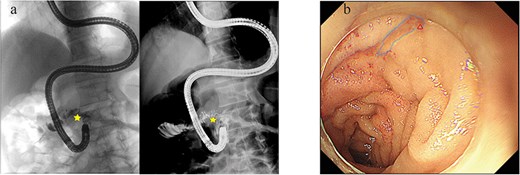

Serosal repair was performed on the stomach and transverse colon, and the duodenal and jejunal perforations were closed primarily. Intraoperative endoscopy facilitated placement of a nasojejunal feeding tube and a duodenal decompression tube. The feeding tube tip was positioned 20 cm distal to the repair site, while the decompression tube tip was advanced to the horizontal portion of the duodenum (Fig. 1c). The patient resumed oral intake 1 week postoperatively. A follow-up endoscopic examination prior to discharge confirmed complete mucosal healing (Fig. 2).

(a) Contrast radiograph of the ascending duodenum and proximal jejunum demonstrating luminal continuity without perforation. (b) Follow-up enteroscope illustrating localized mucosal scarring at the site of duodenal perforation repair.